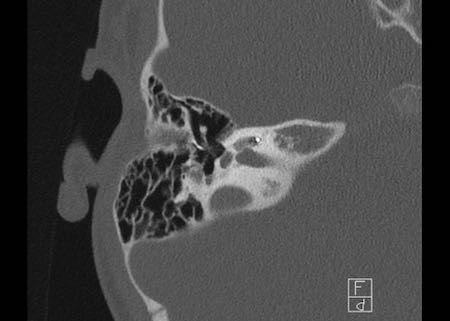

Bên trái là hình ảnh của một bé gái 2 tuổi.

Các hình ảnh từ kết quả chụp CT được thực hiện trước khi cấy ốc tai điện tử.

Quan sát thấy dị dạng nhẹ ở đỉnh ốc tai – không có sự phân tách giữa vòng thứ hai và vòng thứ ba, và trụ ốc tai xương vắng mặt.

Cống tiền đình bình thường.